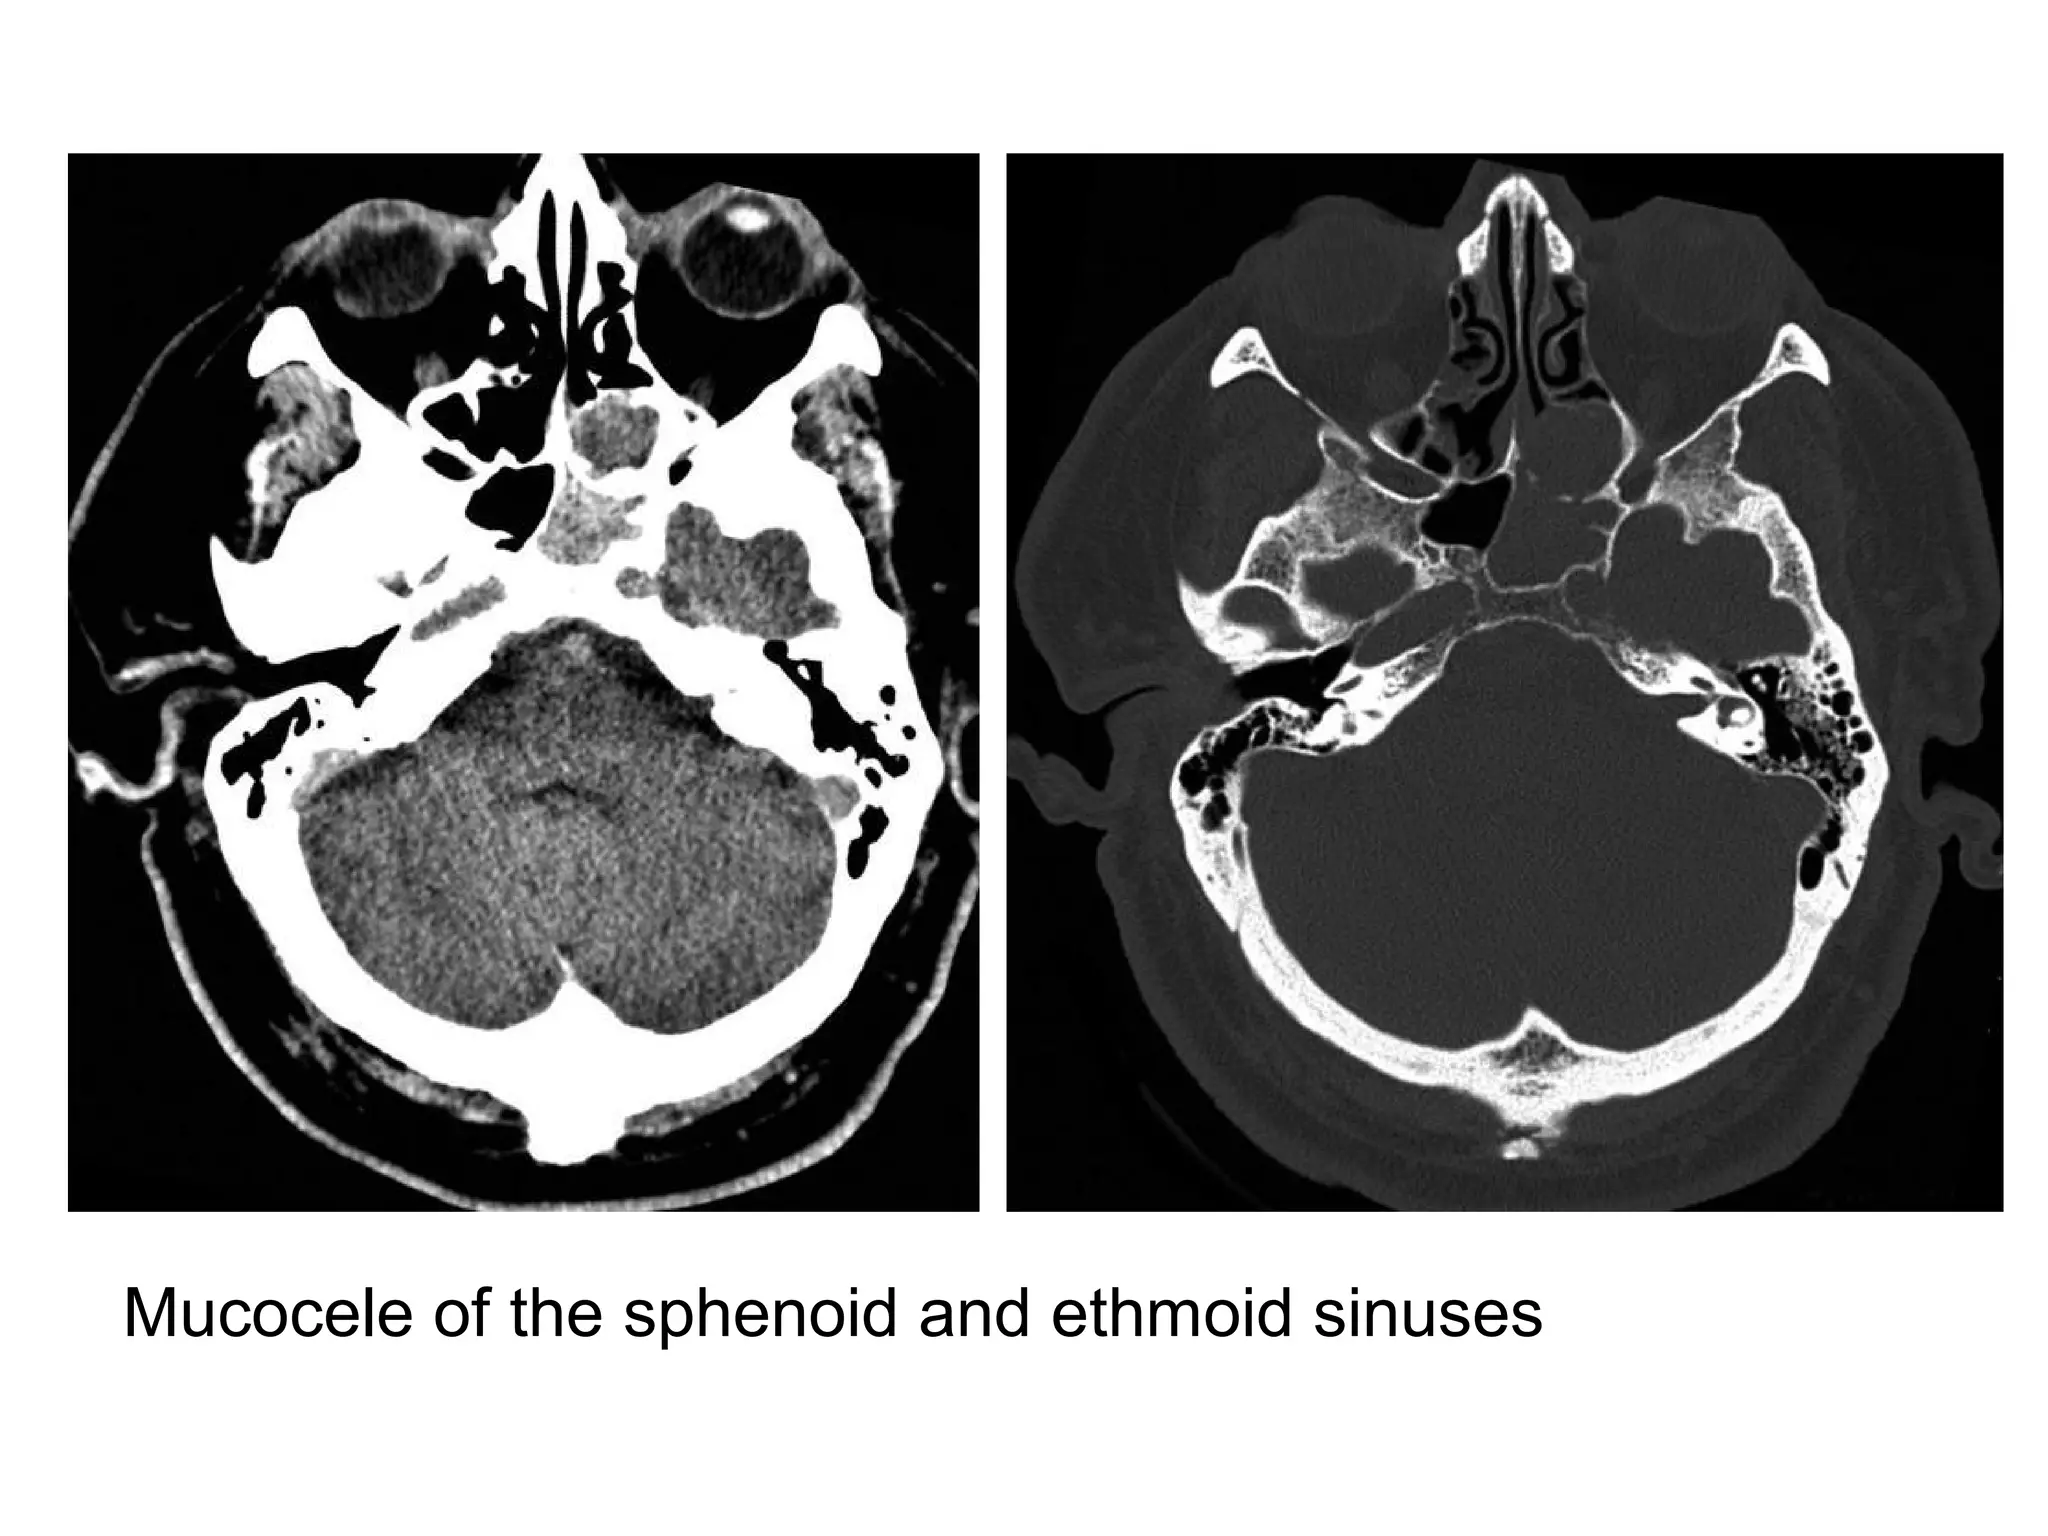

Mucocele of the sphenoid and ethmoid sinuses

Axial unenhanced CT image shows opacification of the left sphenoid

sinus due to a mass (arrow) causing slight expansion of the sinus,

some parts of the sinus wall are thin and some are thick